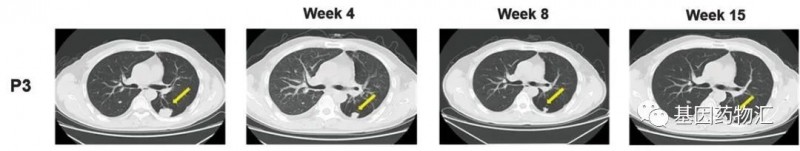

一名患者为50岁的男性,多灶性肝细胞癌病史超过2.2年,GPC3 IHC染色评分3+。

从接受治疗4周开始,这位患者的病灶体积就开始逐渐缩小,至治疗15周时,图中黄色箭头标注的病灶,已经从31.0 × 27.8 mm 逐渐缩小到了 12.2 × 9.5 mm!

CAR-GPC3 T细胞为这位患者带来了长达111天的无进展生存,以及615天的生存期!整个治疗过程中,患者经历的不良反应包括比较轻度的细胞因子释放综合征,以及一些发热。